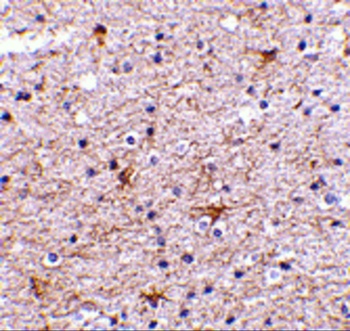

Immunohistochemical staining of human colon cancer using TMED10 antibody